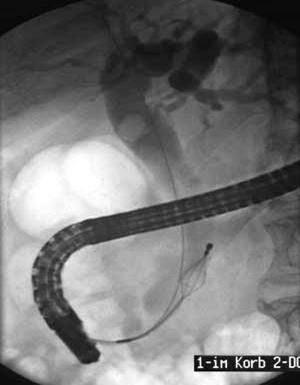

Рисунок 7 – ЭРХПГ: А – холедохолитиаз, введена корзинка Дормия для литоэкстракции; Б – стриктура дистального отдела холедоха с престенотическим расширением